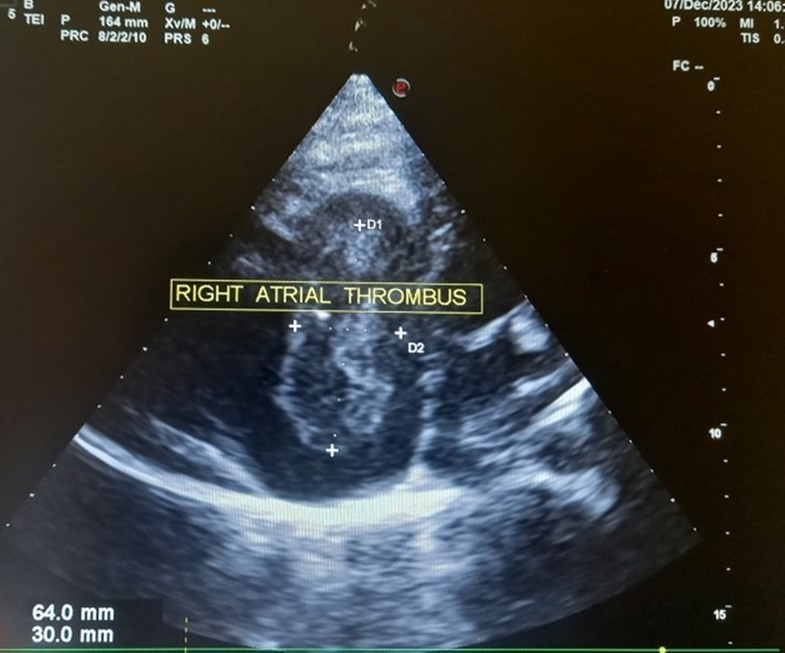

The patient underwent echocardiography (Figure 3 ) showing a low insertion of the septal and posterior leaflets of the tricuspid valve 22 mm below the tricuspid annulus, the anterior leaflet having reduced reduced mobility. Significant dilatation of the the right atrium by atrialisation of the right ventricle (RV). The rudimentary RV and its atrial stump are dilated and responsible for compression of the LV. There was no tricuspid insufficiency. No other associated congenital anomaly. However, we found a large floating thrombus in the right atrium measuring 64 mm x 30 mm in diameter. This was therefore Ebstein's disease at stage C of the Carpentier classification. The apical displacement of the tricuspid septal valve was 22 mm or 15 mm/m2). The surface area of the atrium and the atrialized right ventricle was 45 cm2 , the surface area of the right ventricle and the left cavities was 30 cm2 , the Celermajer index was calculated at 1.4 ( Grade 3).

Figure 3.Transthoracic echocardiography, apical four chambers view . Apical displacement of the tricuspid valve (a) and right atrial thrombus (b).

Transthoracic echocardiography, apical four chambers view . Apical displacement of the tricuspid valve (a) and right atrial thrombus (b).

In our case, the patient had, type C of EA and Grade 2. The investigation also revealed a large thrombus floating in the right atrium and no obvious regurgitation of the tricuspid valve. In addition, the septa was intact, there was no persistence of the ductus arteriosus, the pulmonary and aortic pathway were unobstructed.